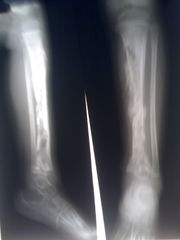

Osteomyelitida (osteomyelitis), česky zánět kostní dřeně, je infekční hnisavé onemocnění kostí a kostní dřeně vyvolané bakteriemi či mykobakteriemi. Při tomto onemocnění dochází k ucpávání cév v kosti krevními sraženinami a následnému odumírání kostní tkáně. Může docházet k obrůstání postižených částí okosticí.

Při exogenním zánětu se infekce do kosti může šířit z okolní hnisající měkké tkáně nebo přímo při otevřených zlomeninách (posttraumatický zánět) či po operacích zavřených zlomenin nebo neúrazových chorob kostí a kloubů (pooperační zánět).